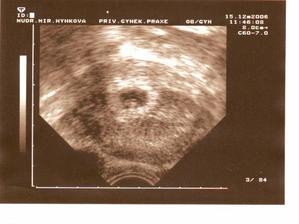

ELIÁŠ

Nejdřív si dával na čas,ale když už se rozhodl,tak snad nechtěl čekat jestli se někam dojede nebo jestli bude vůbec někde volnej flek,dělala jsem co jsem mohla,ale rychleji to fakt nešlo,za 36min.jsme se už všichni na sebe mohli podívat,k velkému překvapení to v tom fofru stihnul i náš tatínek.Bylo to jen den po termínu v pá.10/8 2007,v 14.05h,Eliášek měl 2830g a 50cm,jsme rádi,že porodnice u Apolináře,která byla jasným favoritem,byla i dobrou volbou!